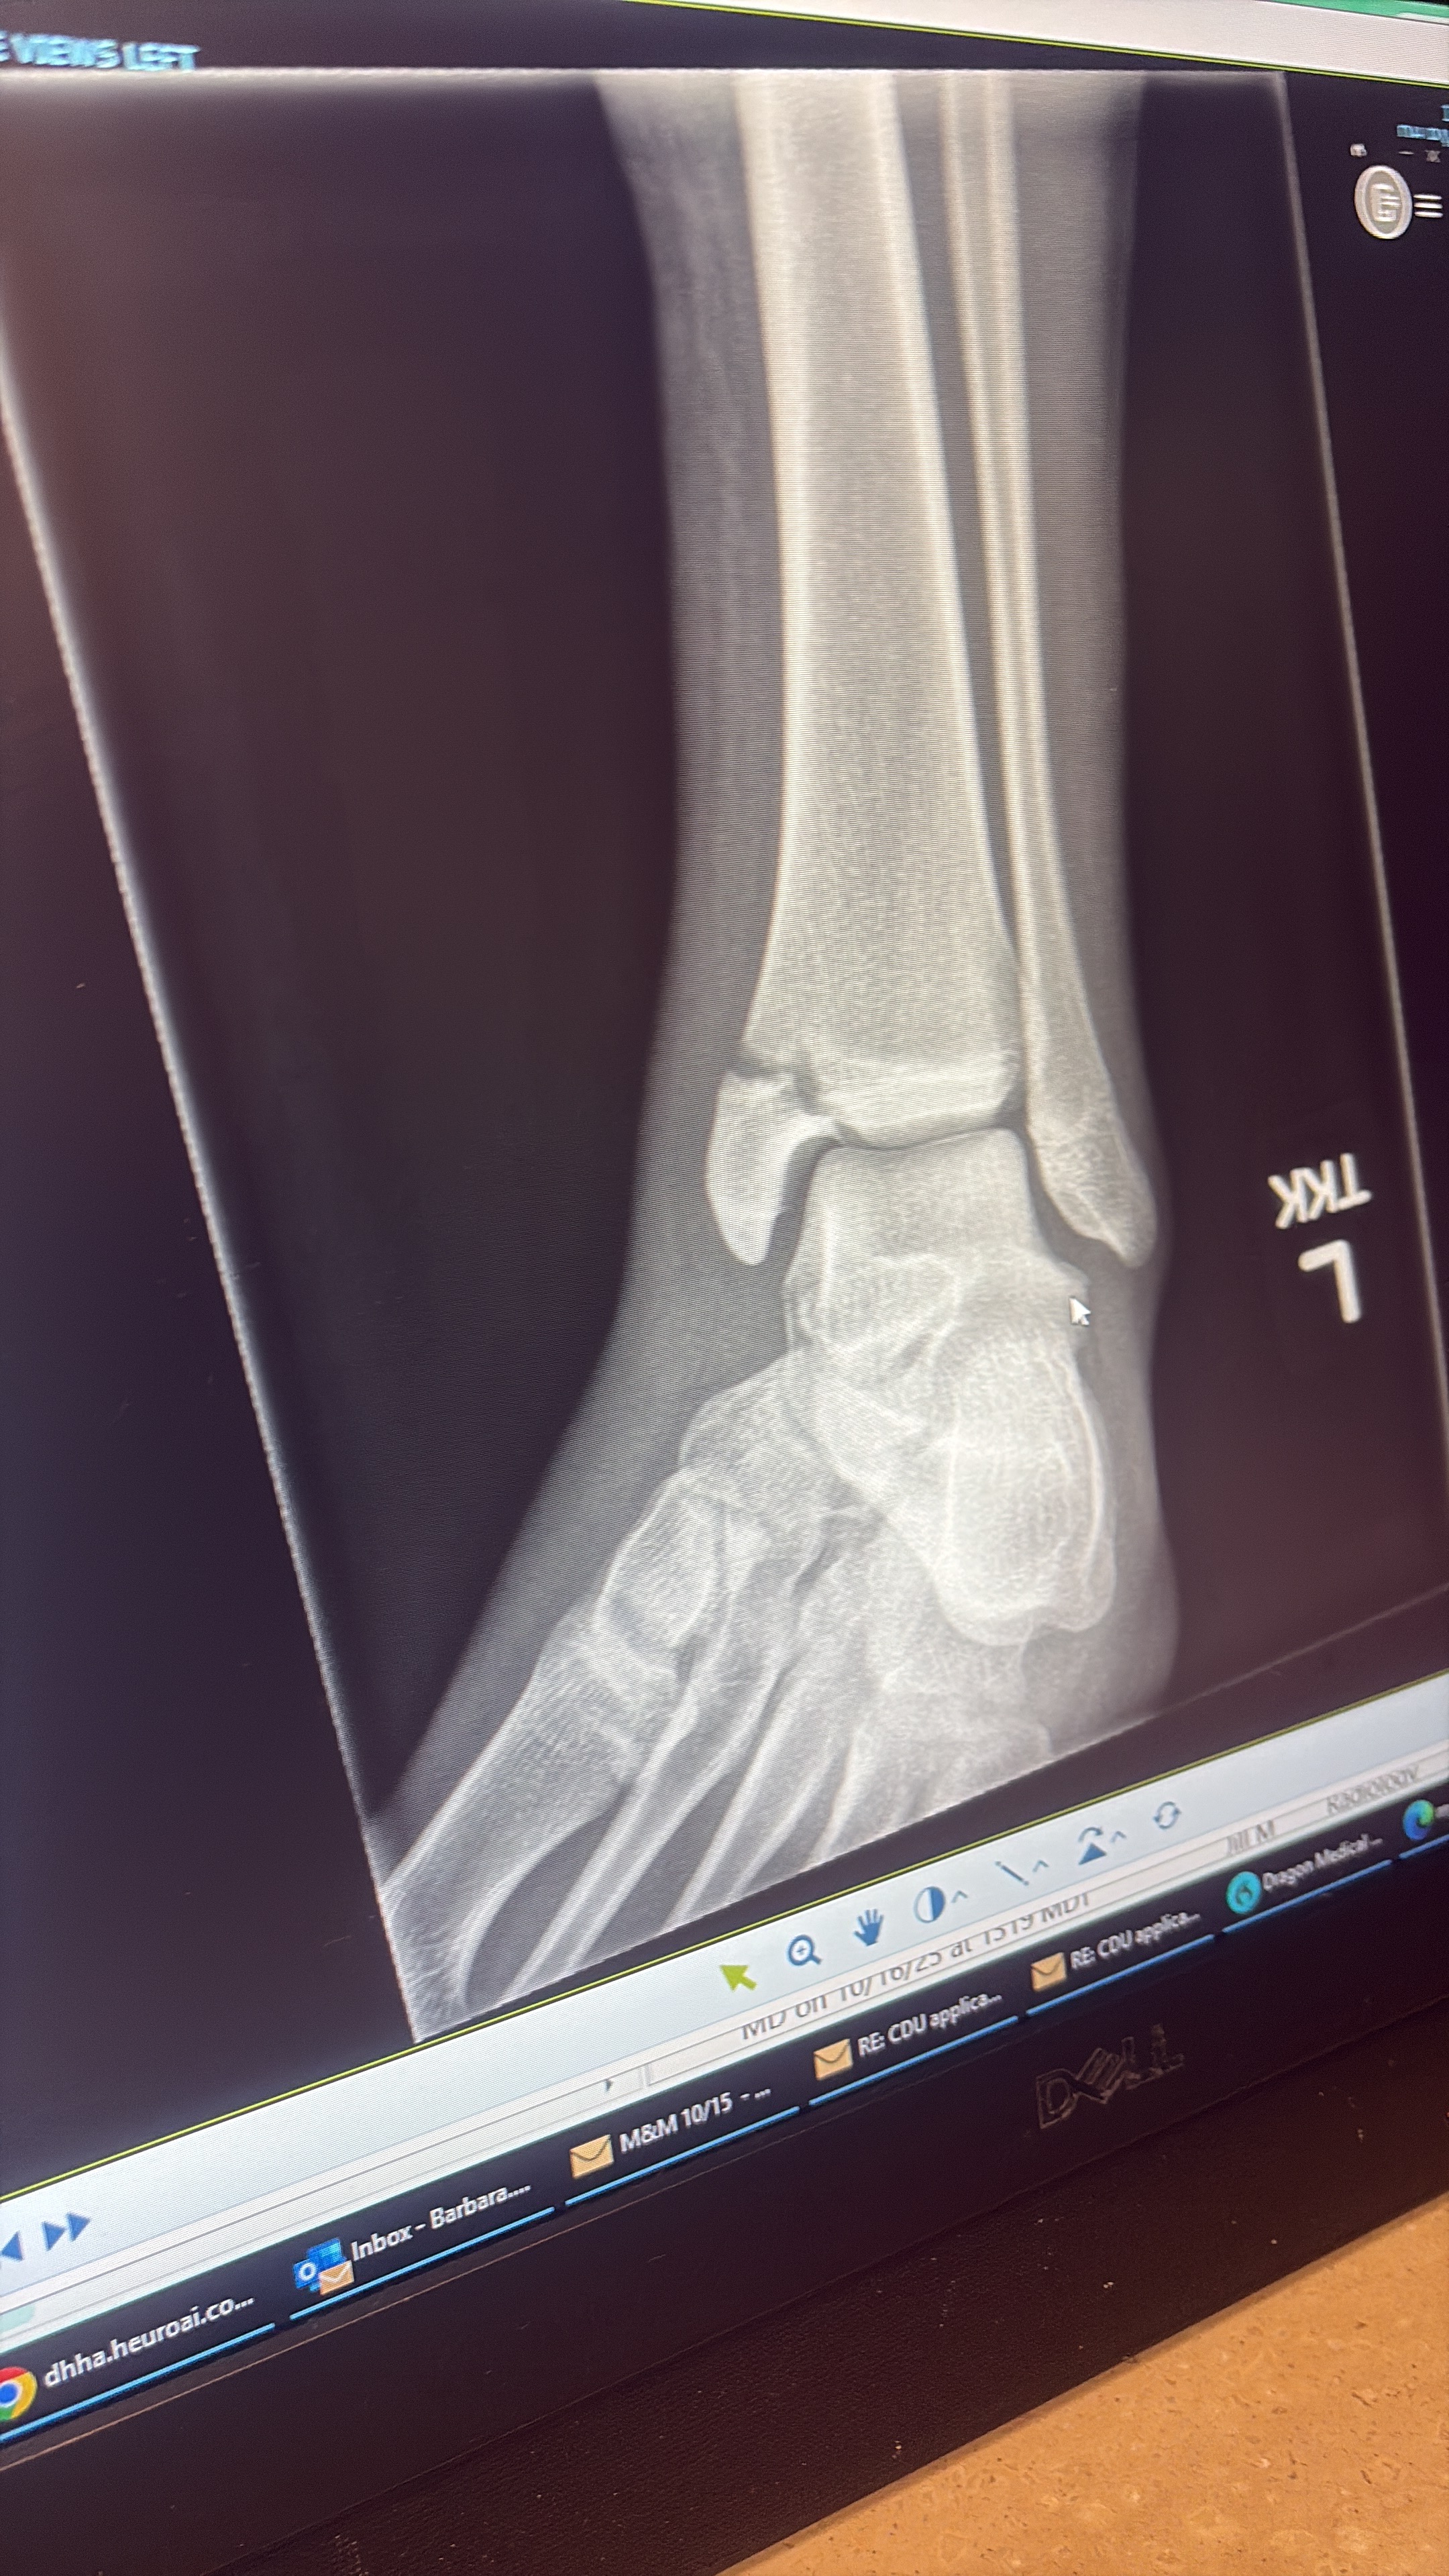

Earlier this year, I suffered a really serious injury during a game versus our rival school. I had a breakaway going to goal and their keeper came out and we collided. Instantly I felt a great amount of pain and my foot started to swell. The pain was so excruciating that I could not return to the game. The next day we went to the doctor, they took x-rays and they told me I had a serious fracture in my leg and needed surgery to put a screw in my leg to fix it.

My parents work very hard to provide for me and my family but are not able to afford the surgery. The doctors told me if I didn't have the surgery that I would never play soccer again and possibly have problems walking for the rest of my life, so they decided to have the surgery anyway. This is bringing a lot of burden to my family financially and would really appreciate any help we can get. I love playing soccer and I love my family for everything that they have done. Please help us if you can, thank you.